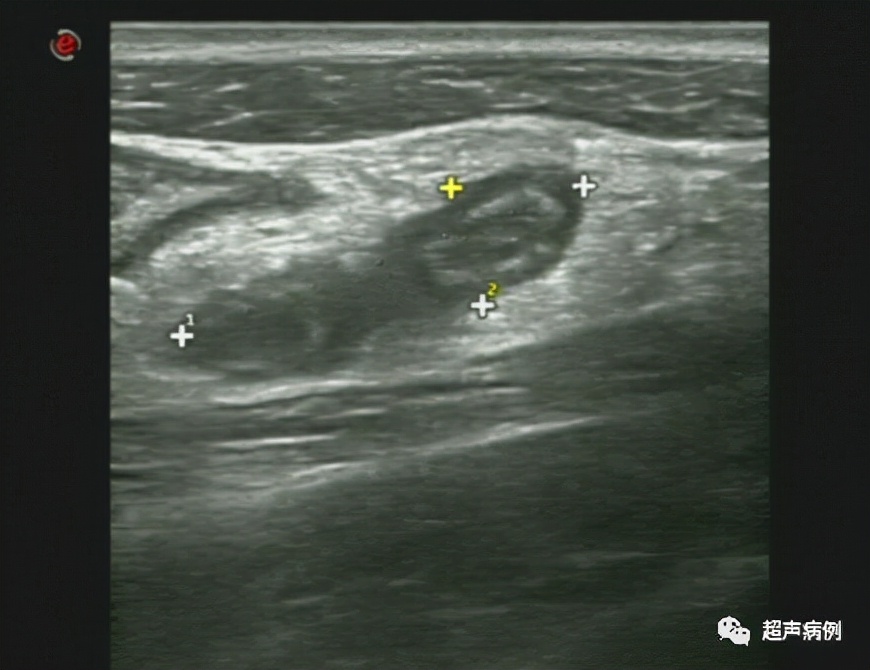

病例2

男,5岁4月。转移性右下腹痛1余天。

超声检查:

在右下腹阑尾解剖区查见范围约2.7x1.1cm管状弱回声,内回声欠均匀,CDFI;边壁可见点状血流信号。其周边组织回声增强。

病理诊断:急性化脓性阑尾炎及其周围炎。